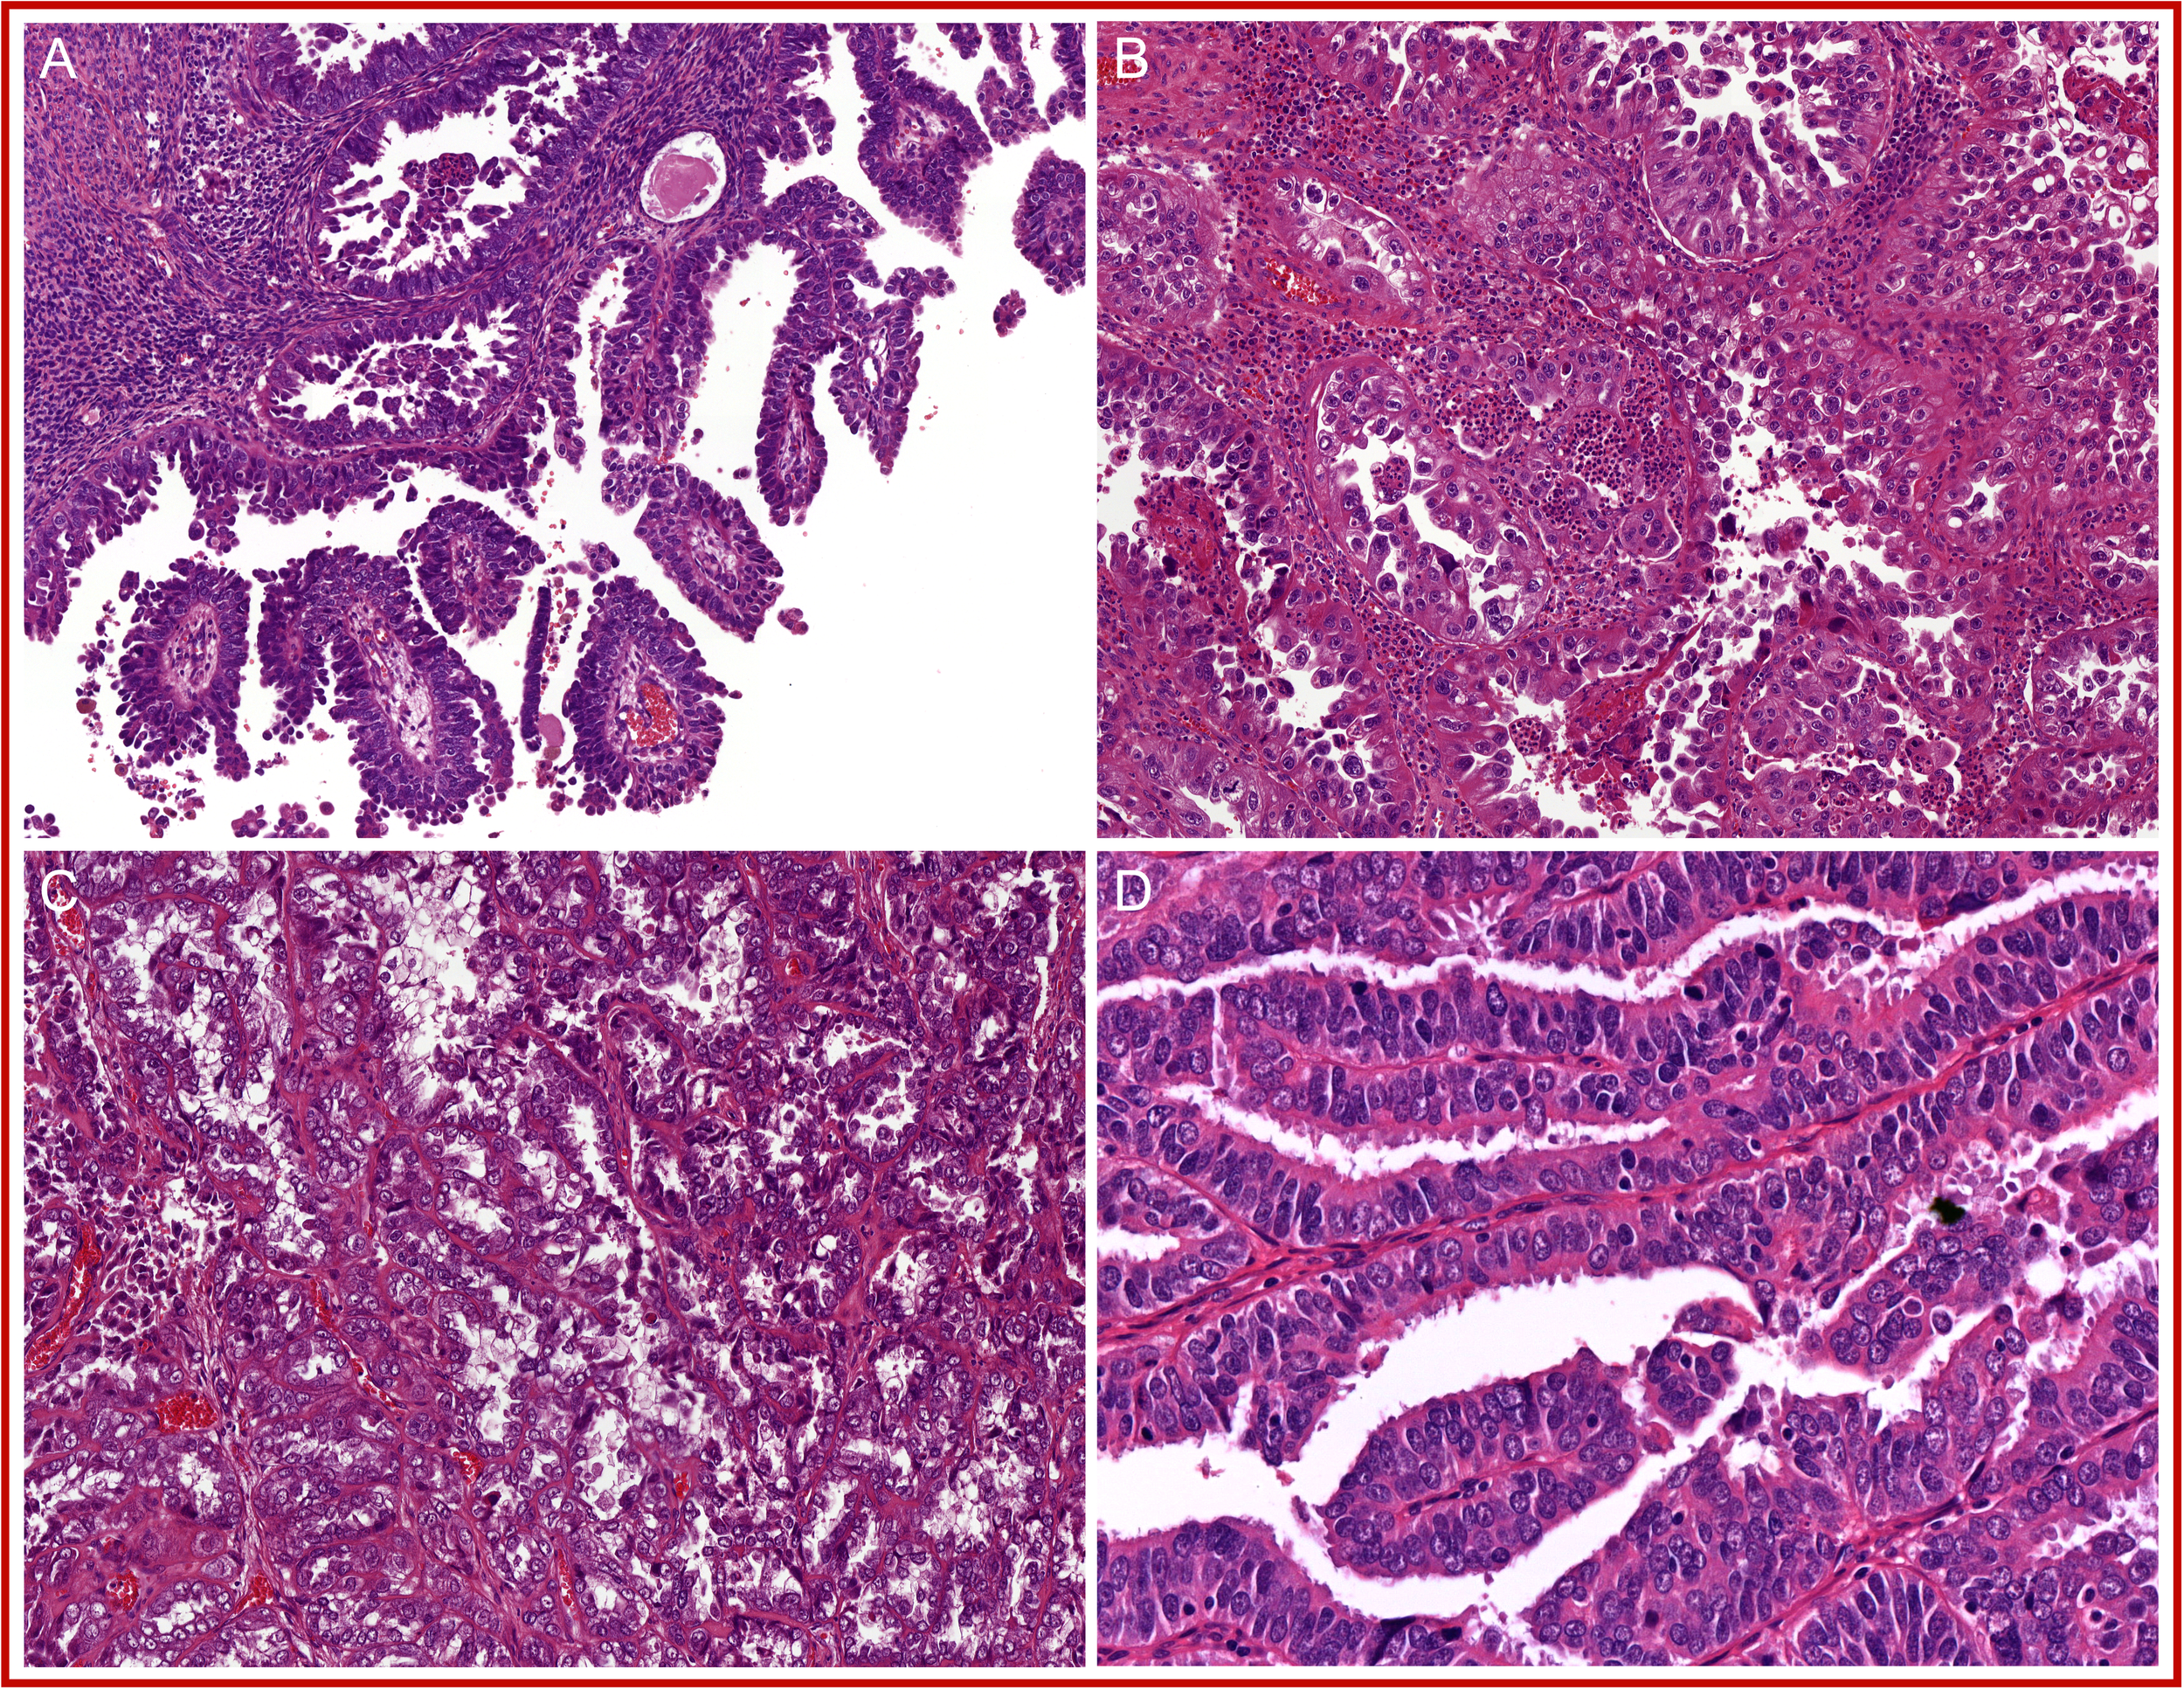

Figure 3

A selection of prototypical morphological features found in POLE-mutated endometrial cancer (POLEmut EC): (A) at least 50% solid growth; (B) hyperchromatic tumor giant cells; (C) a dense peri-tumoral and intra-epithelial infiltrate of lymphocytes; and (D) tertiary lymphoid structures (TLS).